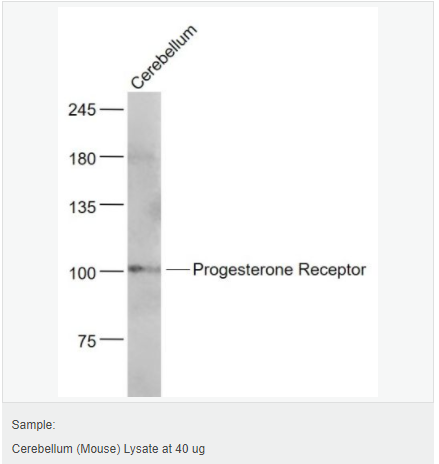

| 英文名稱 | Progesterone Receptor |

| 中文名稱 | 孕激素受體抗體 |

| 交叉反應 | Human, Mouse, Rat, (predicted: Rabbit, ) |

| 產(chǎn)品應用 | WB=1:500-2000 IHC-P=1:100-500 IHC-F=1:100-500 Flow-Cyt=1ug/Test ICC=1:100-500 IF=1:100-500 (石蠟切片需做抗原修復) not yet tested in other applications. optimal dilutions/concentrations should be determined by the end user. |

| 分 子 量 | 103kDa |